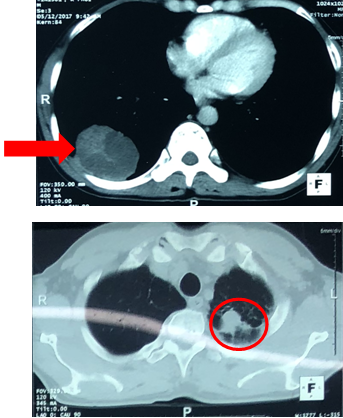

-   Chụp cắt lớp vi tính lồng ngực:

Trước điều trị: U phổi phải kích thước 56x81mm

Sau điều trị: U phổi phải kích thước 35x40mm

Trước điều trị: Khối mờ đỉnh phổi trái kích thước 28mm, nốt mờ thùy dưới phổi trái.

Sau điều trị: Khối mờ đỉnh phổi trái là dải xơ hóa, nốt mờ nhỏ thùy dưới phổi trái không còn.